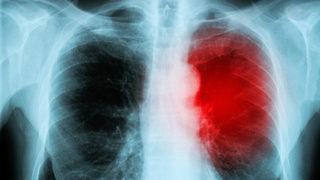

Miyokardit haberleri sayfasında, son dönemde yaşanan önemli gelişmeleri sizlerle paylaşıyoruz. Miyokardit; kalp kasının iltihaplanması sonucu ortaya çıkan bir durumu ifade eder ve ciddi sağlık sorunlarına yol açabilir. Bu sayfada, hastalığın belirtileri, tedavi yöntemleri ve son dakika miyokardit haberleri gibi bilgileri bir araya getiriyoruz. Kullanıcılar için faydalı olabilecek güncel miyokardit haberleri ile hastalığın seyrini yakından takip etme imkanı bulacaksınız.